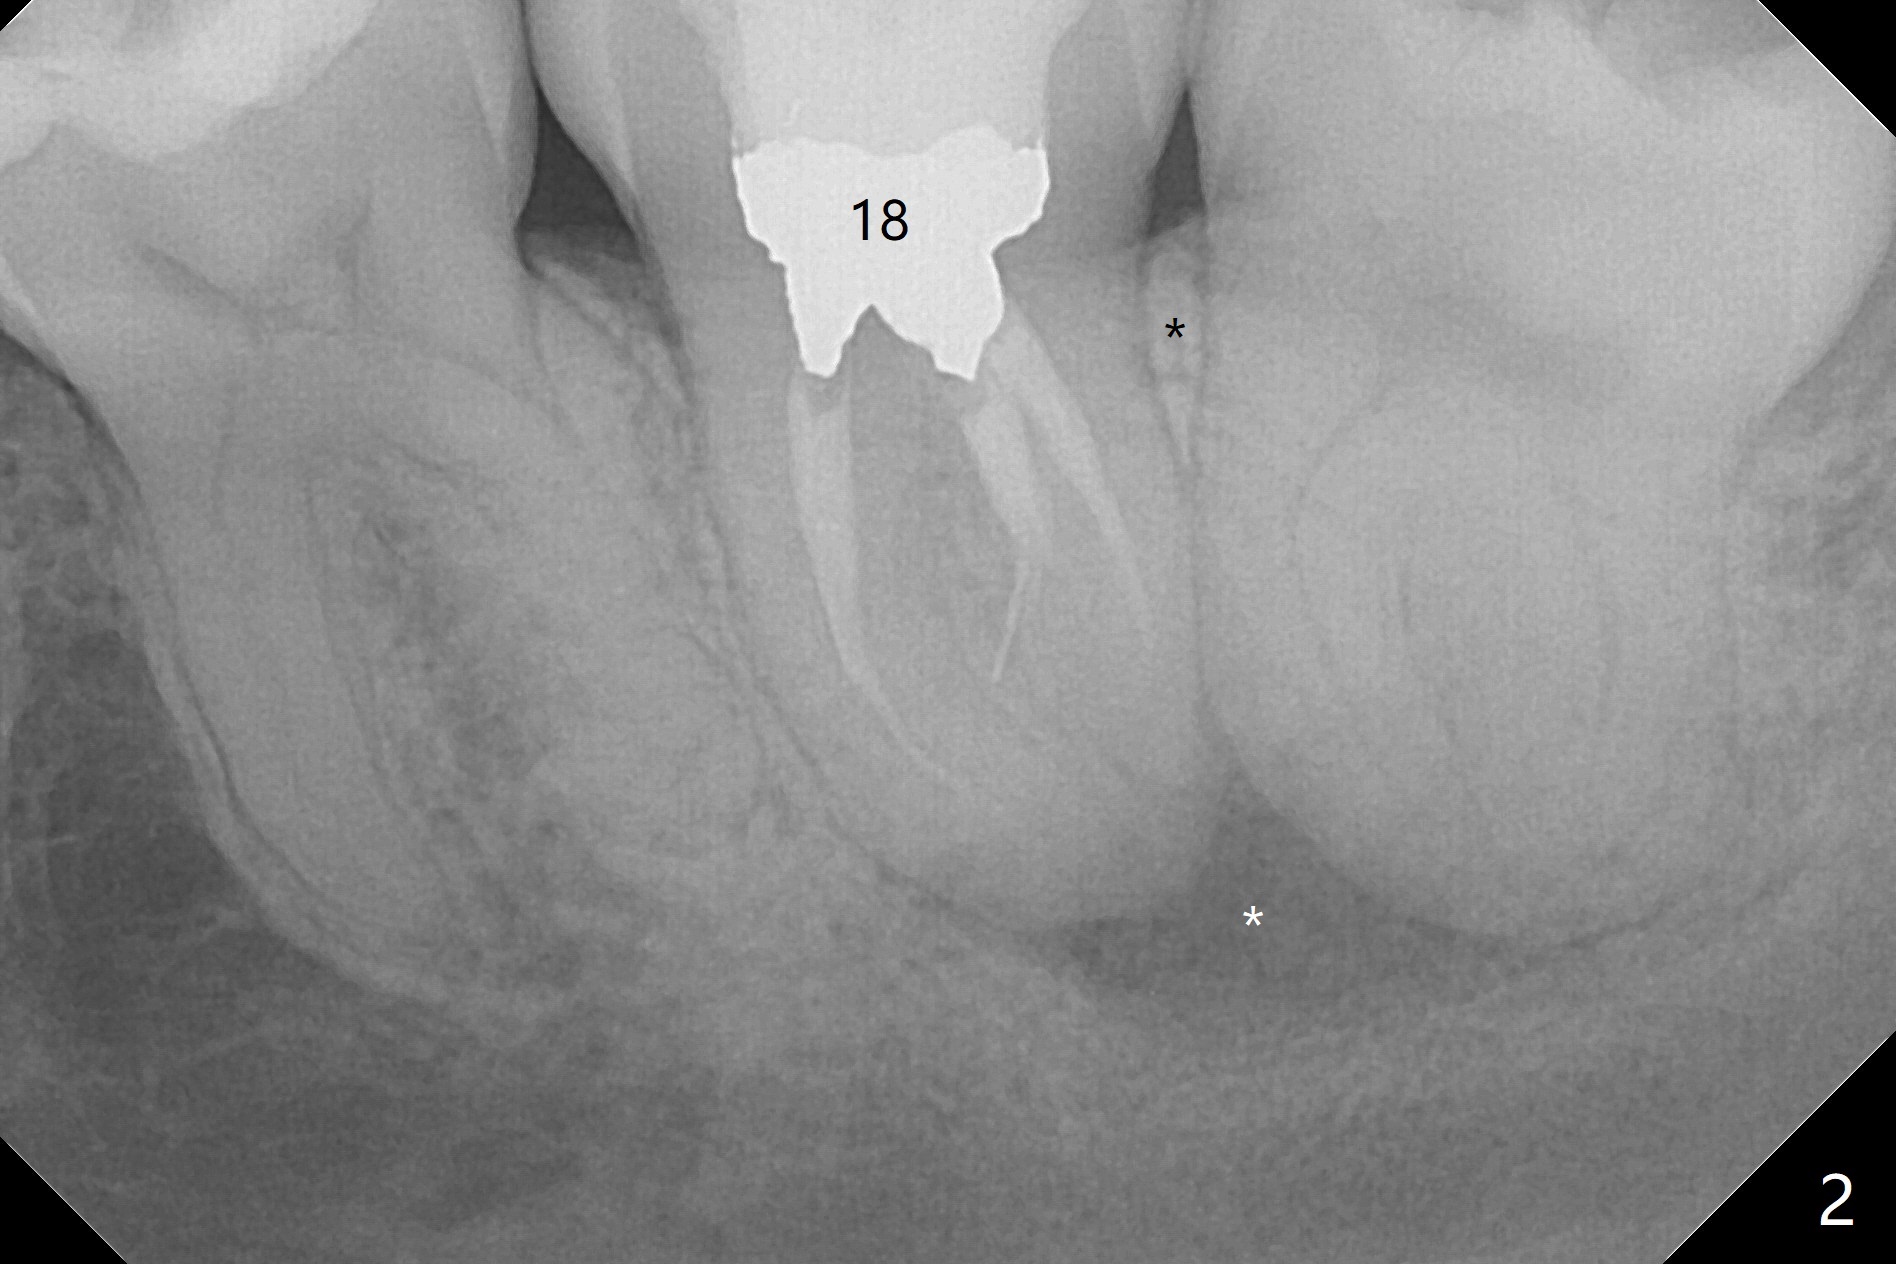

A 37-year-old woman requests extraction of the 3rd molars and orthodontic retreatment (Fig.1). Since the bone between #17 and 18 is thin and short (Fig.2 black *), bone graft is needed after #17 extraction. But the apical infection at #18 (Fig.2 white *) may affect graft survival. The patient agrees to have RCT retreatment done (Fig.3 white curved lines) before extraction (black area). The apical granulation tissue can be removed (Fig.4 red area) prior to bone graft (Augma). The latter will be also placed at #17 as a control. After endodontic consultation, the patient does not want RCT retreatment. She would like to have the 3rd molars extracted first and #18 removed if needed. After #17 extraction (Fig.5), apicoectomy will be performed at #18 (Fig.6 (white outline: surgical bur, use non-torque handpiece)). Following curettage of the apical lesion at #18 (Fig.7), bone graft will be placed (Fig.8 red circles). In fact the patient insists upon #1, 16, 17, and 32 extraction. After extraction, allograft (Fig.9 A (Ossogen, Mineralized Cort/Can (30%/70%), .25-1.0 mm) is placed in the mesioapical of the sockets of #17 and 32, while Osteogen Plug (O) and BioXclude in the distocoronal one (4-0 PGA suture). There is minimal bone between the 2nd and 3rd molars (black arrowheads). The allograft is intentionally pushed into #18 apical defect after enucleation (white arrowhead). The sockets are slightly open, although sutures are in place 2 weeks postop (Fig.10,11). It is unknown whether the bone graft is partially dislodged or not.